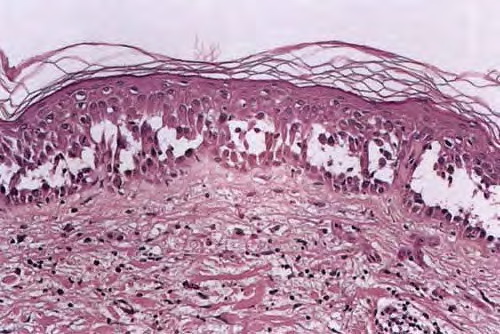

The earliest recognized change may be either eosinophilic spongiosis rarely or, more commonly, “spongiosis” in the lower epidermis . This spongiosis may actually represent the earliest manifestation of acantholysis rather than true spongiosis as defined earlier. Acantholysis leads first to the formation of clefts and then to blisters in a predominantly suprabasallocation . The intraepithelial acantholysis may extend into adnexal structures or occasionally be higher in the stratum spinosum. The basal keratinocytes, although separated from one another through the loss of attachment, remain firmly attached to the dermis like a “row of tombstones.” Within the blister cavity, the acantholytic keratinocytes, singularly or in clusters, have rounded condensed cytoplasm about an enlarged nucleus with peripherally palisaded chromatin and enlarged nucleoli. In some patients, there are varying quantities of antidesmoglein 1 and antidesmoglein 3 antibodies, leading to variable planes of acantholysis. There is little inflammation in the early phase of blister formation. If present, it is usually a sparse, lymphocytic perivascular infiltrate accompanied by dermal edema. However, if eosinophilic spongiosis is apparent, numerous eosinophils may infiltrate the dermis. The phenomenon of eosinophilic spongiosis occurs occasionally in other blistering diseases, particularly in their early phases, including acute contact dermatitis, pemphigus foliaceus, bullous pemphigoid, herpes gestation is, drug eruptions, spongiotic arthropod bite reactions, and transient acantholytic dermatosis. Several important changes ensue as the lesions age. First, a mixed inflammatory cell reaction consisting of neutrophils, lymphocytes, macrophages, and eosinophils may develop. Because of the instability of the blister roof, erosion and ulceration may occur. Older blisters may also have several layers of keratinocytes at the blister base because of keratinocyte migration and proliferation. Last, there may be considerable downward growth of epidermal strands, giving rise to so-called villi (Fig. 9-9D). The evaluation of patients with only oral lesions is difficult, because intact blisters are rarely encountered due to the trauma of mastication, and biopsies may show only erosion and ulceration. Indeed, it is best to sample the edge of a denuded area with intact mucosa in an attempt to demonstrate the typical pathologic changes. Clinicians frequently cannot distinguish between an ulcer and the intact mucosa, as both are often white and shaggy. In patients with only oral lesions, biopsies of intact oral mucosa for DIF testing are more sensitive than biopsies of lesions for routine light microscopic evaluation. Therefore, biopsy from the normal maxillary and upper buccal mucosa is necessary when there is extensive ulceration. Cytologic examination using a Tzanck preparation is useful for the rapid demonstration of acantholytic epidermal keratinocytes in the blisters of pemphigus vulgaris. For this